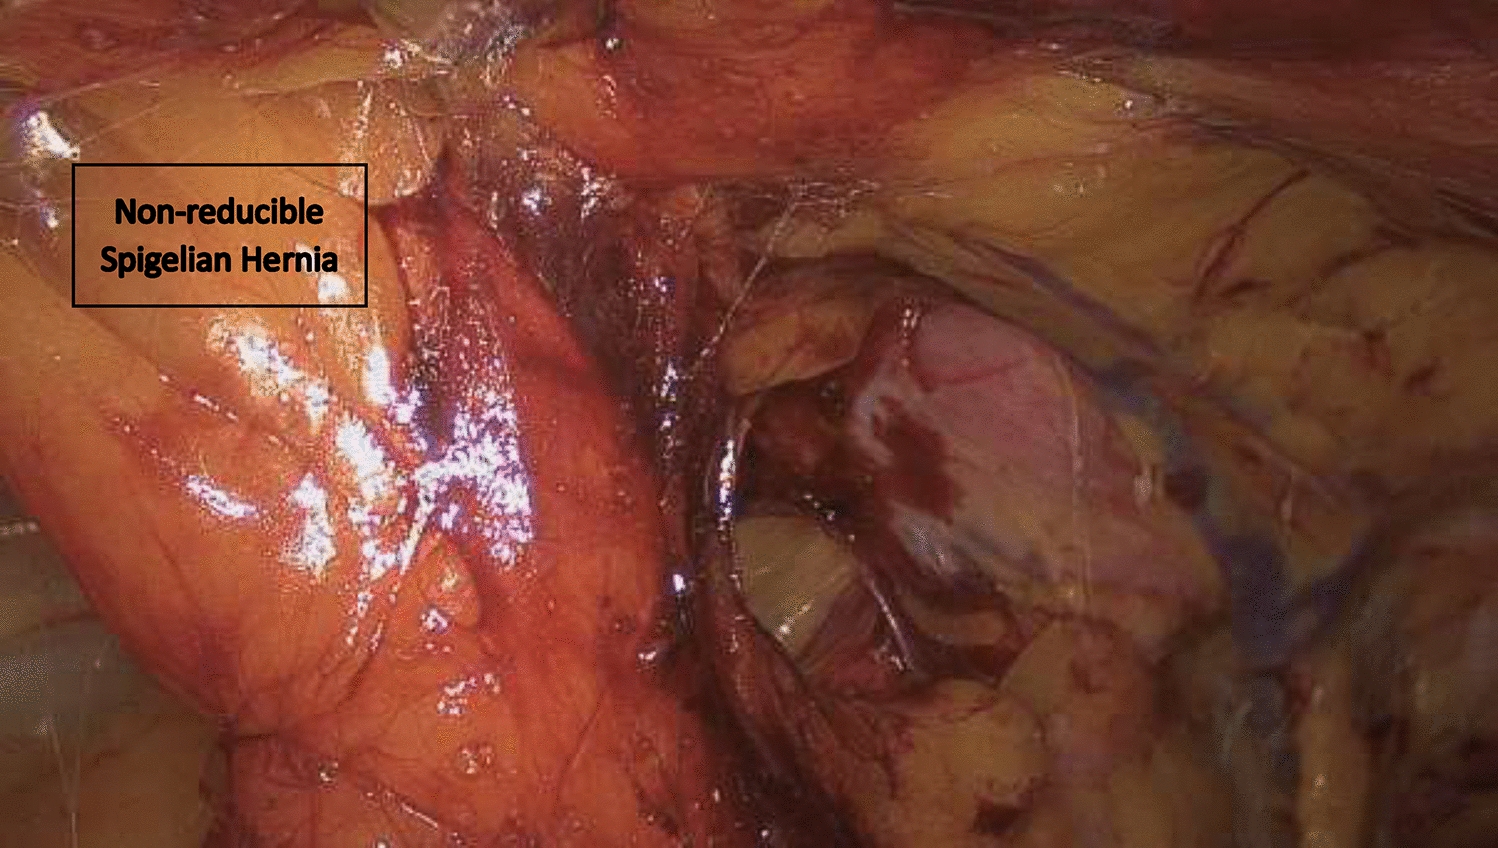

• Figs. 6, 7, 8, 9, 10: intraoperative findings and repair steps with mesh insertion in selected cases

Fig. 9

Endoscopic view on non-reducible spigelian hernia (Foto

© U. Volmer)

Bild vergrößern